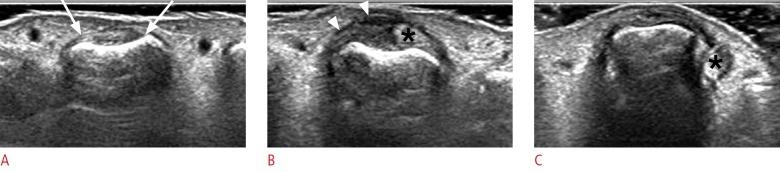

The recent development of advanced high-resolution transducers has enabled the fast, easy, and dynamic ultrasonographic evaluation of small, superficial structures such as the finger. In order to best exploit these advances, it is important to understand the normal anatomy and the basic pathologies of the finger, as exemplified by the following conditions involving the dorsal, volar, and lateral sections of the finger: sagittal band injuries, mallet finger, and Boutonnière deformity (dorsal aspect); flexor tendon tears, trigger finger, and volar plate injuries (volar aspect); gamekeeper's thumb (Stener lesions) and other collateral ligament tears (lateral aspect); and other lesions. This review provides a basis for understanding the ultrasonography of the finger and will therefore be useful for radiologists.

先进的高分辨率换能器的最新发展使得对手指等小而浅表结构进行快速、简便和动态的超声评估成为可能。为了充分利用这些进展,了解手指的正常解剖结构和基本病变非常重要,以下列举了累及手指背侧、掌侧和侧方的一些情况,包括:矢状带损伤、锤状指和纽扣畸形(背侧);屈肌腱撕裂、扳机指和掌板损伤(掌侧);守猎者拇指(斯滕纳损伤)和其他侧副韧带撕裂(外侧);以及其他病变。这篇综述为理解手指的超声检查提供了基础,因此对放射科医生非常有用。